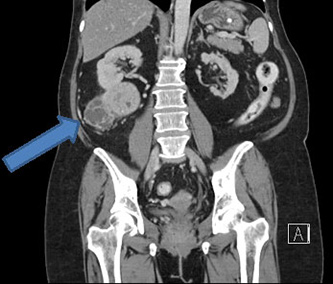

Cancer treatment options such as chemotherapy, radiotherapy, nano-medicine, and surgery are among the many techniques available to cancer patients. However, the large volume of research in this field has given birth to a new range of issues, such as choosing the appropriate implementation, and the often high cost of such treatments. Among the many treatments routinely prescribed to cancer patients are anti-angiogenic drugs such as tyrosine kinase inhibitors (TKIs). Such drugs are extremely expensive, and may cause numerous side-effects in the patient. Therefore, a reliable anti-angiogenic predictor which can help determine the projected outcomes of such treatments may be highly useful. Researchers from the Institute of Bioengineering and Nanotechnology (IBN), Singapore General Hospital (SGH), and National Cancer Centre Singapore (NCCS) have developed a test kit which they believe will help to address these concerns, in patients diagnosed with clear cell renal cell carcinoma (ccRCC), one of the three major types of kidney cancer.

According to the study in European Eurology, the researchers have developed a practical, eight-gene assay which is able to determine the particular subtype of the measured ccRCC sample. The researchers performed a whole-genome expression analysis on samples with material from 55 ccRCC patients, and compiled the results into different categories, with different probable responses to treatment. The assay may be used to distinguish patients into groups with different survival and treatment outcomes, by comparing their particular ccRCC profile to the research conducted in the study. Patients suffering from renal cell carcinoma may benefit from this technology, as it may determine the potential for a successful anti-angiogenic TKI implementation, as well as the survival potential of the patient. In light of the high price of TKIs, and the threat of potential side-effects, the test kit could prove to be a highly beneficial piece of technology.